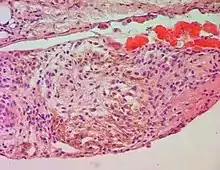

Histopathology of a case of chronic pulmonary congestion, showing a siderophage (white arrow, characterized by coarse brown pigment, which is slightly refractile), and interstitium with edema, hemosiderin deposition (black arrow) and collagenous thickening.

A siderophage is a hemosiderin-containing macrophage. Heart failure cells are siderophages generated in the alveoli of the lungs of people with left heart failure or chronic pulmonary edema, when the high pulmonary blood pressure causes red blood cells to pass through the vascular wall.[1] Siderophages are not specific of heart failure. They are present wherever red blood cells encounter macrophages, such as pulmonary hemorrhage.

In left heart failure, the left ventricle can not keep pace with the incoming blood from the pulmonary veins. The resulting backup causes increased pressure on the alveolar capillaries, and red blood cells leak out. Alveolar macrophages (dust cells) engulf the red blood cells, and become engorged with brownish hemosiderin.

In chronic pulmonary edema, alveolar septa become thick and fibrous, again increasing pressure on alveolar capillaries and resulting in leakage of red blood cells which undergo phagocytosis by alveolar macrophages.